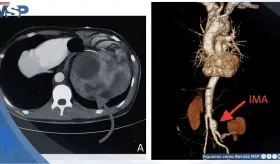

La compresión de la arteria coronaria principal izquierda (LMCA) por dilatación de la arteria pulmonar representa una complicación subdiagnosticada de la hipertensión pulmonar severa, con prevalencia del 6%.